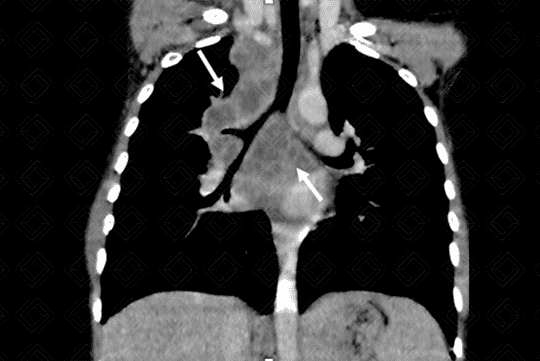

Texto alternativo para a imagem Figura 1. Créditos: Dra Elazir Mota - Rio de Janeiro/RJ

Descrição da lesão: Radiografia de tórax PA (figura 1): observa-se alargamento do mediastino na região hilar direita (seta vermelha) com consequente afilamento do brônquio-fonte deste lado (cabeças das setas vermelhas).